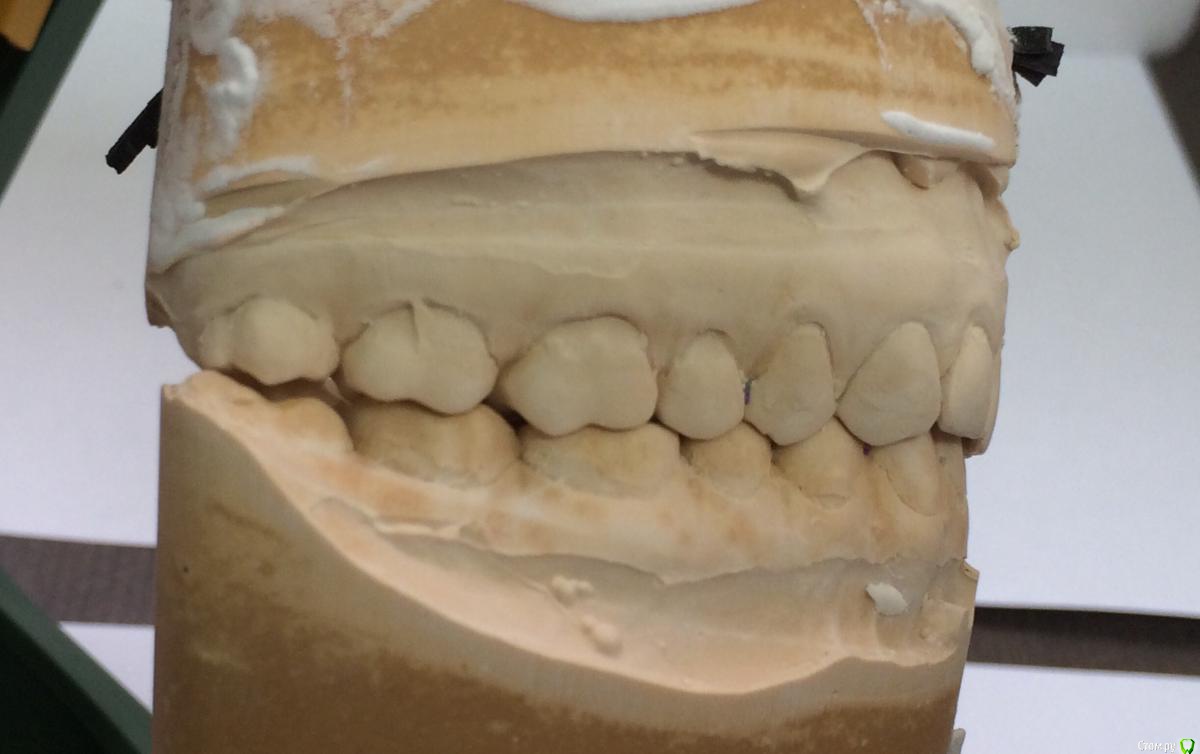

Larnary Опубликовано 28 июля, 2015 Поделиться Опубликовано 28 июля, 2015 (изменено) Добрый день!Ко мне обратилась пациент 1988 гр с жалобой на стираемость зубов и постоянные сколы пломб.Объективно небная поверхность верхних резцов стерта до дентина. Окклюзионная стираемость жевательной группы зубов.Прошу помочь с выявлением причины такой стираемости зубов и оптимальноно метода лечения Изменено 28 июля, 2015 пользователем Larnary Ссылка на комментарий

Larnary Опубликовано 28 июля, 2015 Автор Поделиться Опубликовано 28 июля, 2015 (изменено) Видно окклюзионнык интерференции в области 37 и 47.На днях удален 38 и дальше будут удалены остальные восьмерки. На ТРГ мне видится небольшая ретрузия верхних резцов,дистальный прикус. Так же левпя окклюзионная кривая более выраженная,чем правая Изменено 28 июля, 2015 пользователем Larnary 1 Ссылка на комментарий

PLAY Опубликовано 28 июля, 2015 Поделиться Опубликовано 28 июля, 2015 Загипсовано в центральном соотношении? Ссылка на комментарий

Larnary Опубликовано 28 июля, 2015 Автор Поделиться Опубликовано 28 июля, 2015 (изменено) в центральной окклюзии Изменено 28 июля, 2015 пользователем Larnary Ссылка на комментарий